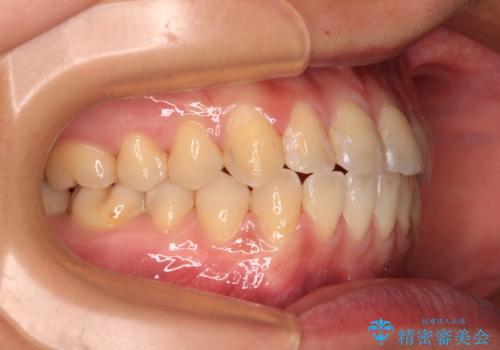

前歯のクロスバイトを治したい ワイヤー装置による矯正治療

クロスバイト改善まではスムーズに進みましたが、その後は強い舌の突出癖によりオープンバイトの期間が長く続きました。

舌のトレーニングをしっかりと実施してもらい、何とか仕上げることができました。